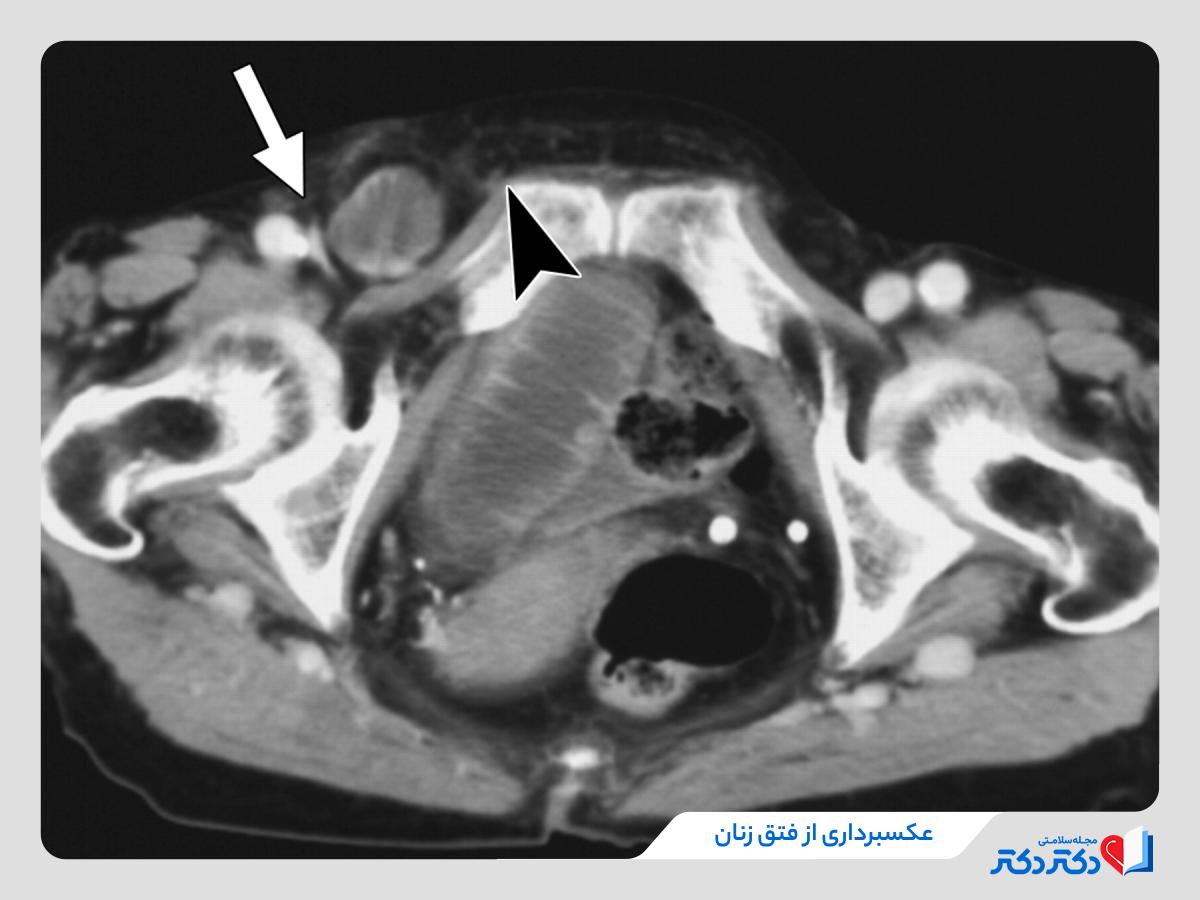

[ad_1] نوشته و ویرایش شده توسط مجله ی رنگو باد فتق در زنان یکی از اختلالات نسبتا کمتر شناخته‌شده اما مهم در حوزه پزشکی است که به علت تفاوت‌های آناتومیک با مردان، ویژگی‌ها و چالش‌های خاص خود را دارد. این عارضه وقتی رخ می‌دهد که بافت یا اندامی از داخل شکم، از طریق نقطه‌ای ضعیف در دیواره شکم یا کشاله ران به بیرون سختی آورده و تبدیل برآمدگی می‌بشود. اگرچه شیوع آن در زنان کمتر از مردان است، اما خطر ابراز عوارضی همانند گیر افتادن یا خفگی محتویات فتق در…